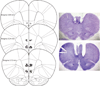

Objectives: Because the medial prefrontal cortex (mPFC) plays an important role in relapse to cocaine and methamphetamine seeking, we tested the effects of lidocaine inactivation of prelimbic (PL) and infralimbic (IL) subregions of mPFC on cue-induced relapse to MDMA seeking.

Methods: Rats were trained to respond for MDMA infusions (0.50 mg/kg/infusion, i.v.) paired with a discrete cue in daily 2-h sessions. Responding was reinforced contingent on a modified fixed ratio 5 schedule of reinforcement. Cue-induced reinstatement tests were conducted after responding was extinguished in the absence of MDMA and the conditioned cues. Prior to reinstatement tests, rats received bilateral microinjections of either lidocaine (100 μg/0.5 μl/side) or physiological saline (0.5 μl/side) delivered to either PL or IL mPFC.

Results: Microinjections of lidocaine into PL completely blocked reinstatement of MDMA-seeking behavior compared with saline microinjections into the same region. Lidocaine microinjections did not, however, have an effect on food-maintained responding, ruling out a nonspecific disruption of motor performance. Conversely, lidocaine inactivation of IL had no effect on reinstatement of MDMA seeking or food-maintained responding.